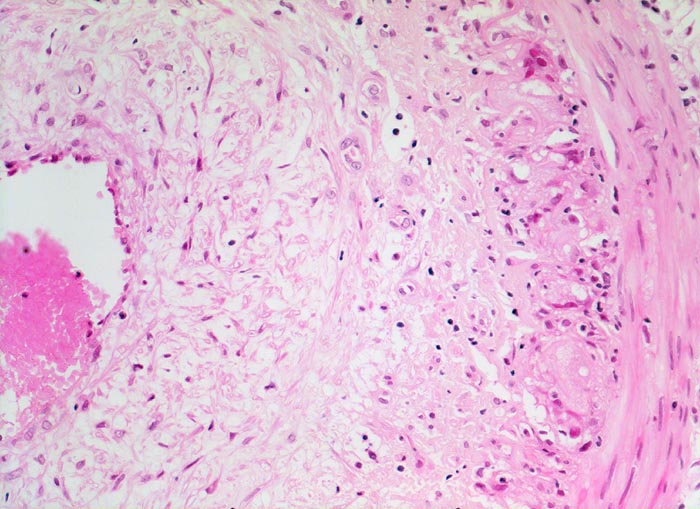

Arteritis temporalis Horton (Riesenzellarteriitis)

Arteria temporalis

Ausgeprägte lockere Intimafibrose. Die Media ist deutlich dünner als die Intima. An der Grenze zwischen Media und Intima Reste einer stark fragmentierten Lamina elastica interna und ein gemischtes Entzündungsinfiltrat.

Seit mehreren Monaten starke beidseitige Schläfenkopfschmerzen. Seit einigen Tagen zusätzlich symmetrische muskelkaterartige Schmerzen im Schulterbereich und am Gesäss. Druckschmerzhaftigkeit der Oberarme. Druckschmerzhafte und pulslose Temporalarterien. Stark erhöhte Blutsenkungsgeschwindigkeit. Biopsie der Temporalarterien und Einleitung einer Corticosteroidtherapie bei dringendem Verdacht auf Horton Arteritis.